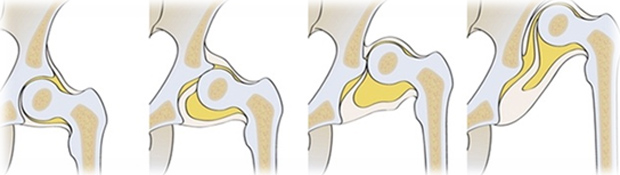

Εξάρθρημα του ισχίου σημαίνει η κεφαλή του μηριαίου να μην βρίσκεται εντός της υποδοχής της κοτύλης, μέσα στη λεκάνη, αλλά εκτός. Αυτό συμβαίνει γιατί η κοτύλη δεν είναι αρκετά βαθειά για να το συγκρατεί και έχει φορά λοξή, ώστε γλιστράει και «φεύγει» προς τα επάνω.

Σε περιπτώσεις που δεν πηγαίνει η κεφαλή στη θέση της ή παρ΄ όλη τη θεραπεία η κοτύλη εξακολουθεί να είναι αβαθής και λοξή, υπάρχει μία σειρά χειρουργικών επεμβάσεων (κοτυλοπλαστικές, οστεοτομίες) που τείνουν να την διορθώσουν.